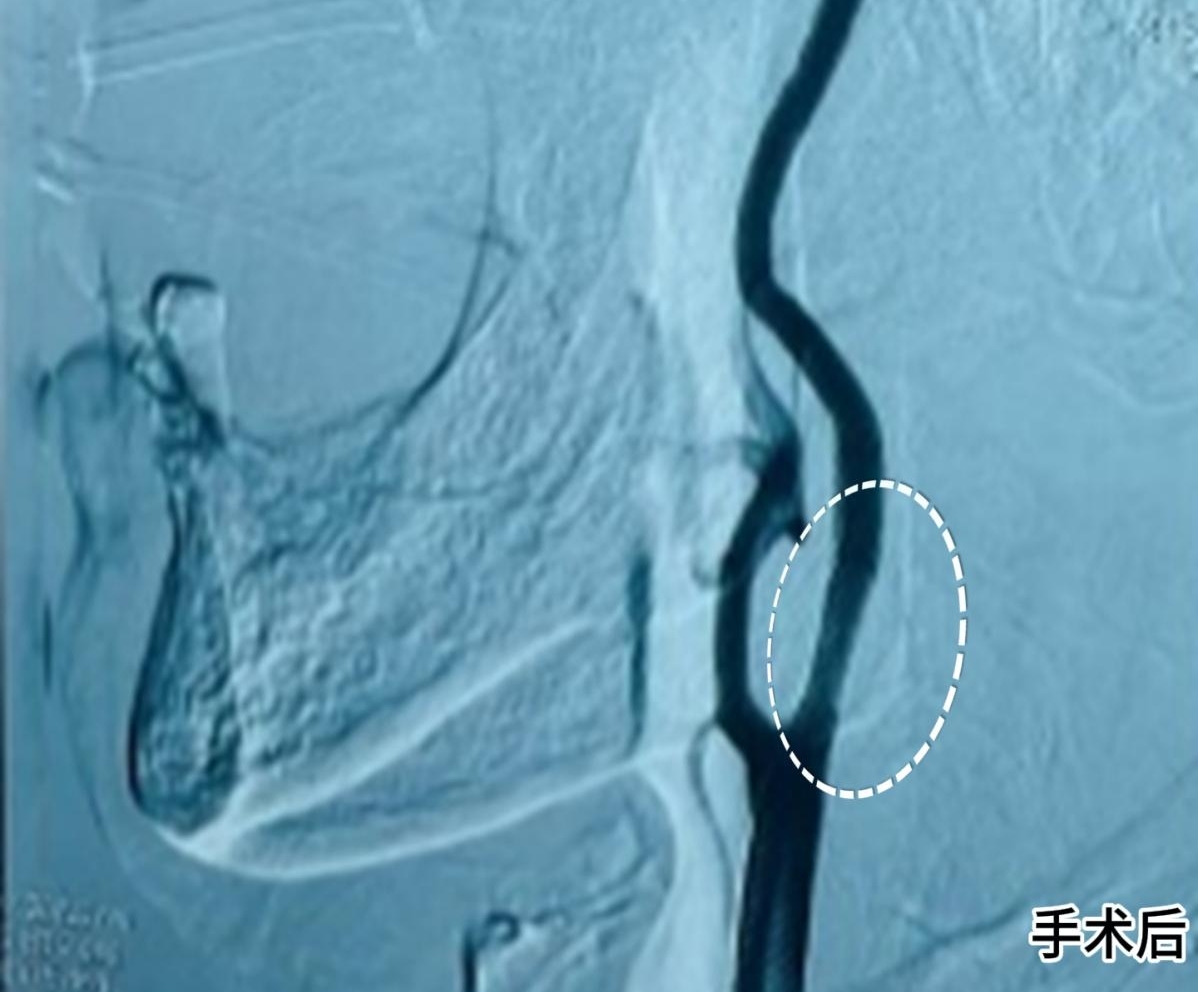

手术由司君增副主任医师主刀,在局麻状态下,团队通过股动脉穿刺建立微小通路,将介入器械精准送达狭窄部位。“老年患者血管往往存在迂曲钙化,器械推送难度极大,我们借助高清血管造影系统实时导航,确保支架定位误差不超过 1 毫米。” 司君增介绍。整个手术历时 40 分钟,术后即刻造影显示,大爷闭塞的颈动脉完全再通,血流恢复正常。

在神经内一科医护团队的精细化管理下,患者术后未出现任何并发症,血压稳定、肢体肌力逐步恢复,观察 3 天后顺利出院。“没想到这么大年纪还能手术成功,真是给了老爷子第二次生命!” 家属握着医护人员的手再三致谢。